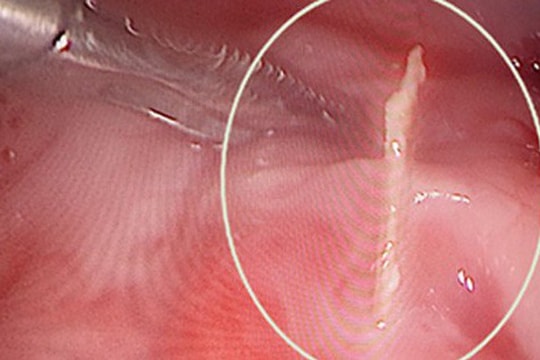

Vô tình nuốt dị vật niềng răng khi uống nước, bé gái 11 tuổi được nôi soi gây mê khẩn

Một bệnh nhi 11 tuổi ở Hải Phòng trong lúc uống nước đã vô tình nuốt phải dị vật dùng để cố định hàm sau niềng răng và được các bác sĩ Bệnh viện Trẻ em Hải Phòng nội soi gây mê, gặp bỏ dị vật thành công.